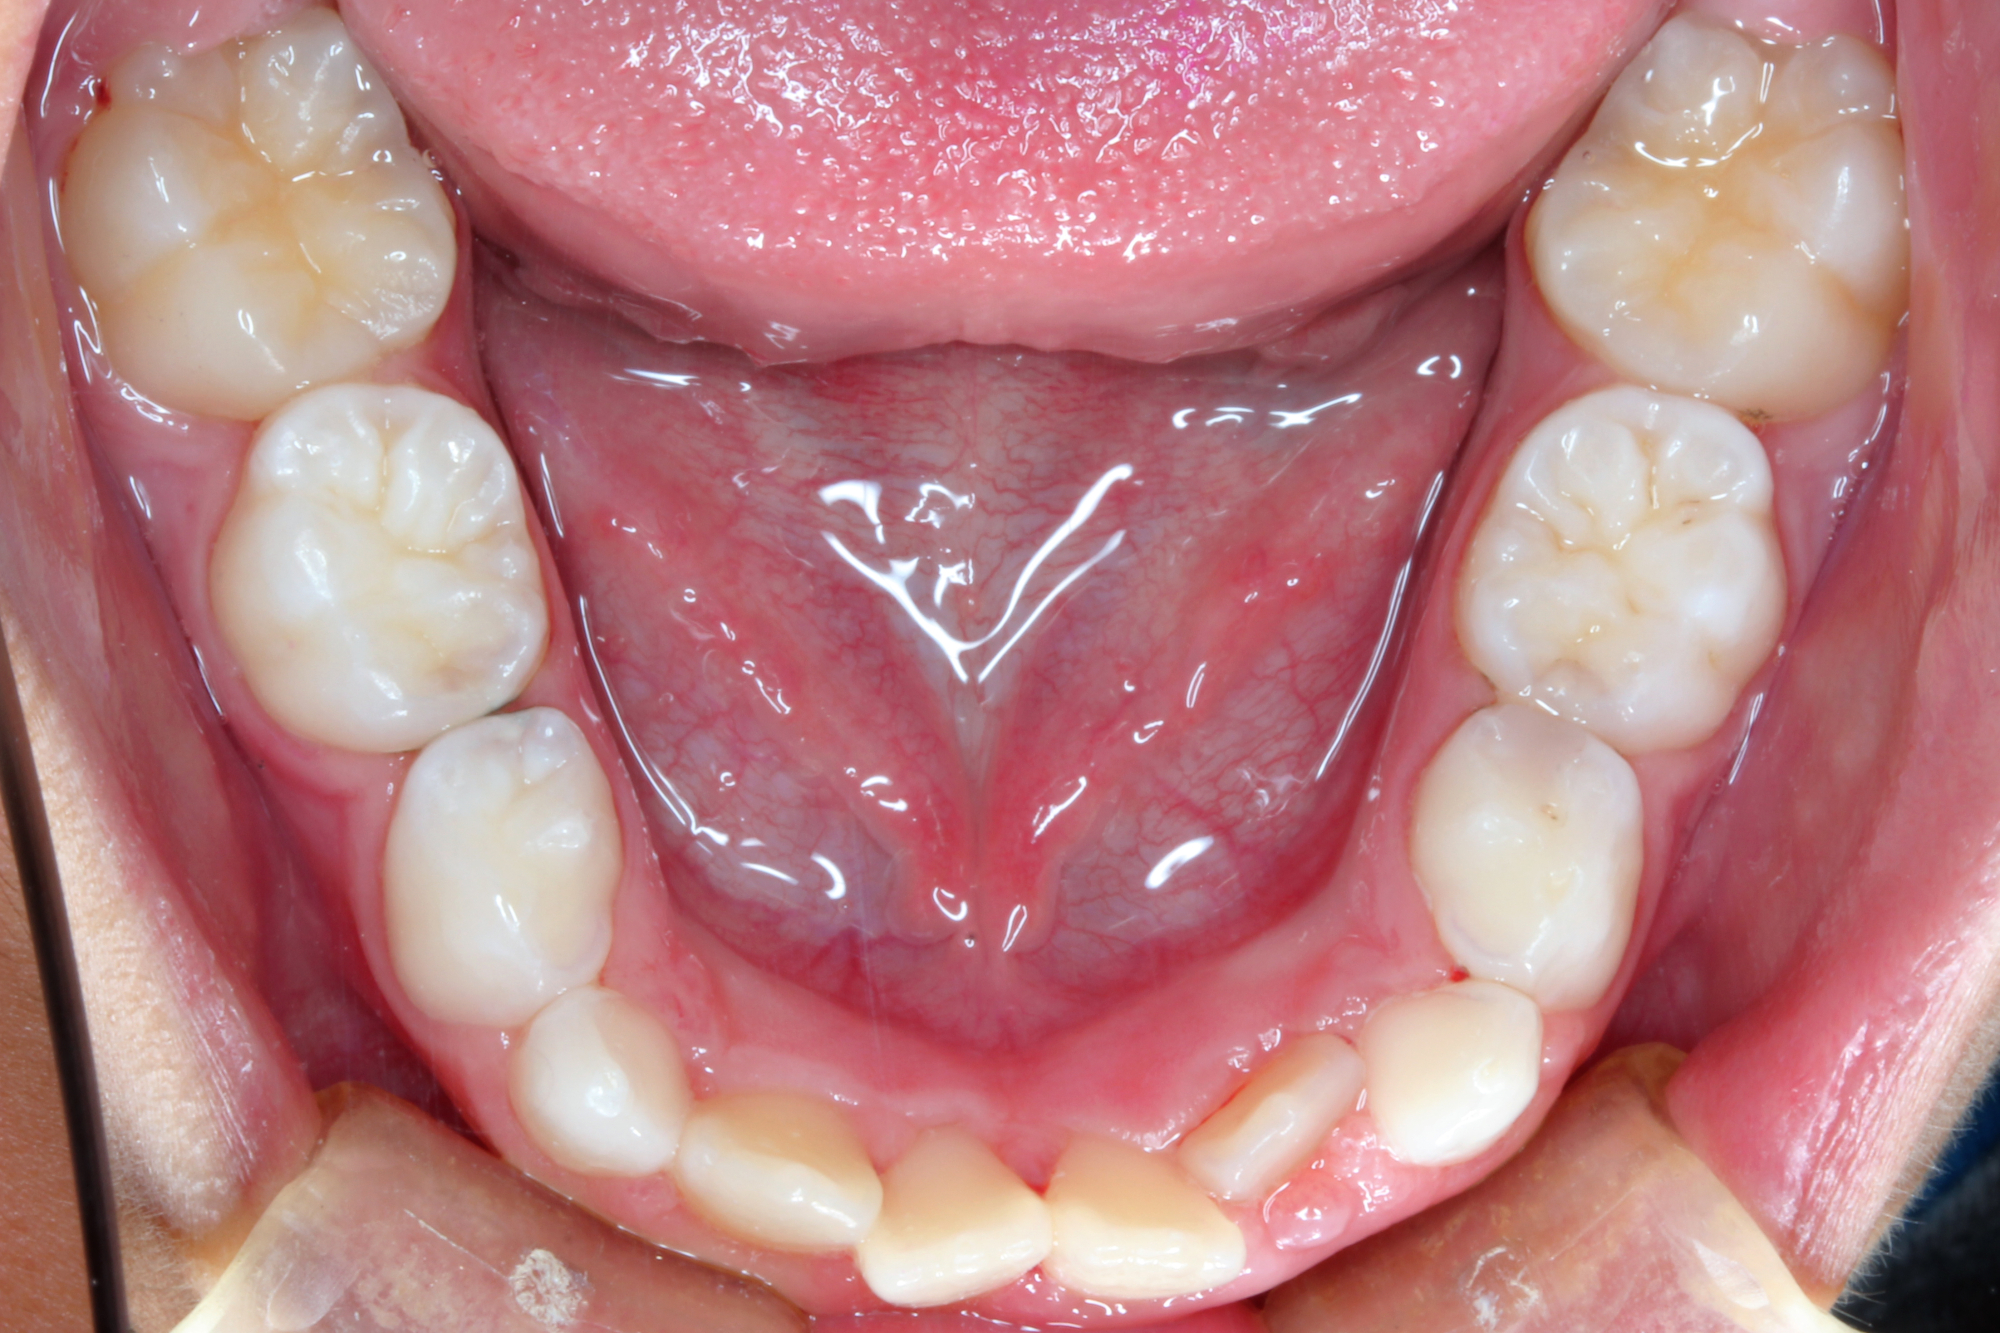

日本で行われている拡大床治療にも色々な方法がありますが当院での特長は最初に永久歯に生え替わる上下4本の前歯を奥歯の生え替わりが始まる前までに顎を拡大してきれいに並べることです。そのため拡大床治療の期間は小学校1年生頃から4、5年生頃までの間に限定しており、それまでに目的が達成できない場合には別の治療法に移行します。またゆっくりスペースを獲得するようにしているのも特長で2週間に1回ネジを回すようにしています。一般的には1週間にⅠ回ないし2回ネジを回すことが多いようです。ゆっくり進めるので一日の装着時間はお家にいるときと寝ている間だけにしています。学校や自宅以外での装着はせずゆっくり拡大していくので治療期間が長くなりますが後戻りは少なく確実になります。治療開始時期が大切ですので時期を逸した場合には拡大床治療は行いません。一般的に拡大床治療の評判が悪いのは開始時期が遅く、いつまでも治療を長引かせ治らないことによるものが多いようです。 拡大床治療はスペースを作って永久歯がならぶスペースを作ることが目標ですので細かい歯の向きや角度まで整えられないこともあります。そんな場合には別の矯正治療が必要になります。

拡大床治療で顎のスペースを拡げられるのは11歳くらいまでです。そのため個人差はありますが遅くても小学校2年生までに始めなければなりません。下の前歯が生え替わりはじめた頃から下の前歯が4本、上の前歯が2本生え替わる頃までが始め時です。すでに上下4本とも生え替わってしまった場合にはすでに遅いことが多くあります。